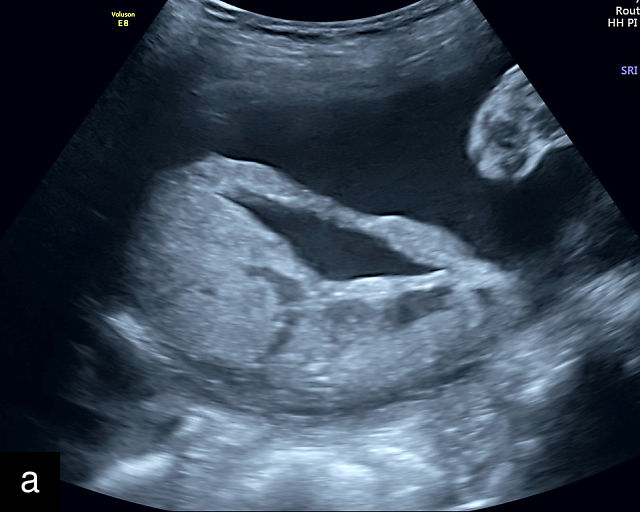

Normal ultrasound appearance of the placenta

Placental characteristics by trimester: thickness, echogenicity and location

In the early first trimester, trophoblastic tissue appears as an echogenic ring encircling the gestational sac (Figure 1a). By the late first trimester, the placenta becomes recognizable as a distinct structure on ultrasound (Figure 1b). Initially, it presents as a homogeneous echogenic mass (Figure 1b–d) but undergoes progressive differentiation, becoming more heterogeneous as pregnancy advances from the second to third trimester (Figure 1e–g). By the third trimester, cotyledons become discernible, and in the late third trimester, calcifications frequently appear basally and around the cotyledons (Figure 1g).

1

Ultrasound images of development of the placenta (P/p). (a) Trophoblastic tissue appearing as an echogenic ring surrounding the gestational sac at 6 weeks' gestation. (b) Placenta at 12 weeks has become a discrete, uniformly echogenic mass. (c) Placenta at 17 weeks. (d) Placenta at 20 weeks. (e) Placenta at 27 weeks. (f) Placenta at 33 weeks. Increasingly, differentiation and heterogeneous appearance is seen, with demarcation of the cotyledons. Basal calcifications are beginning to appear. (g) Placenta at 40 weeks, showing a distinctly heterogeneous appearance, with clear demarcation of the cotyledons and presence of calcifications.